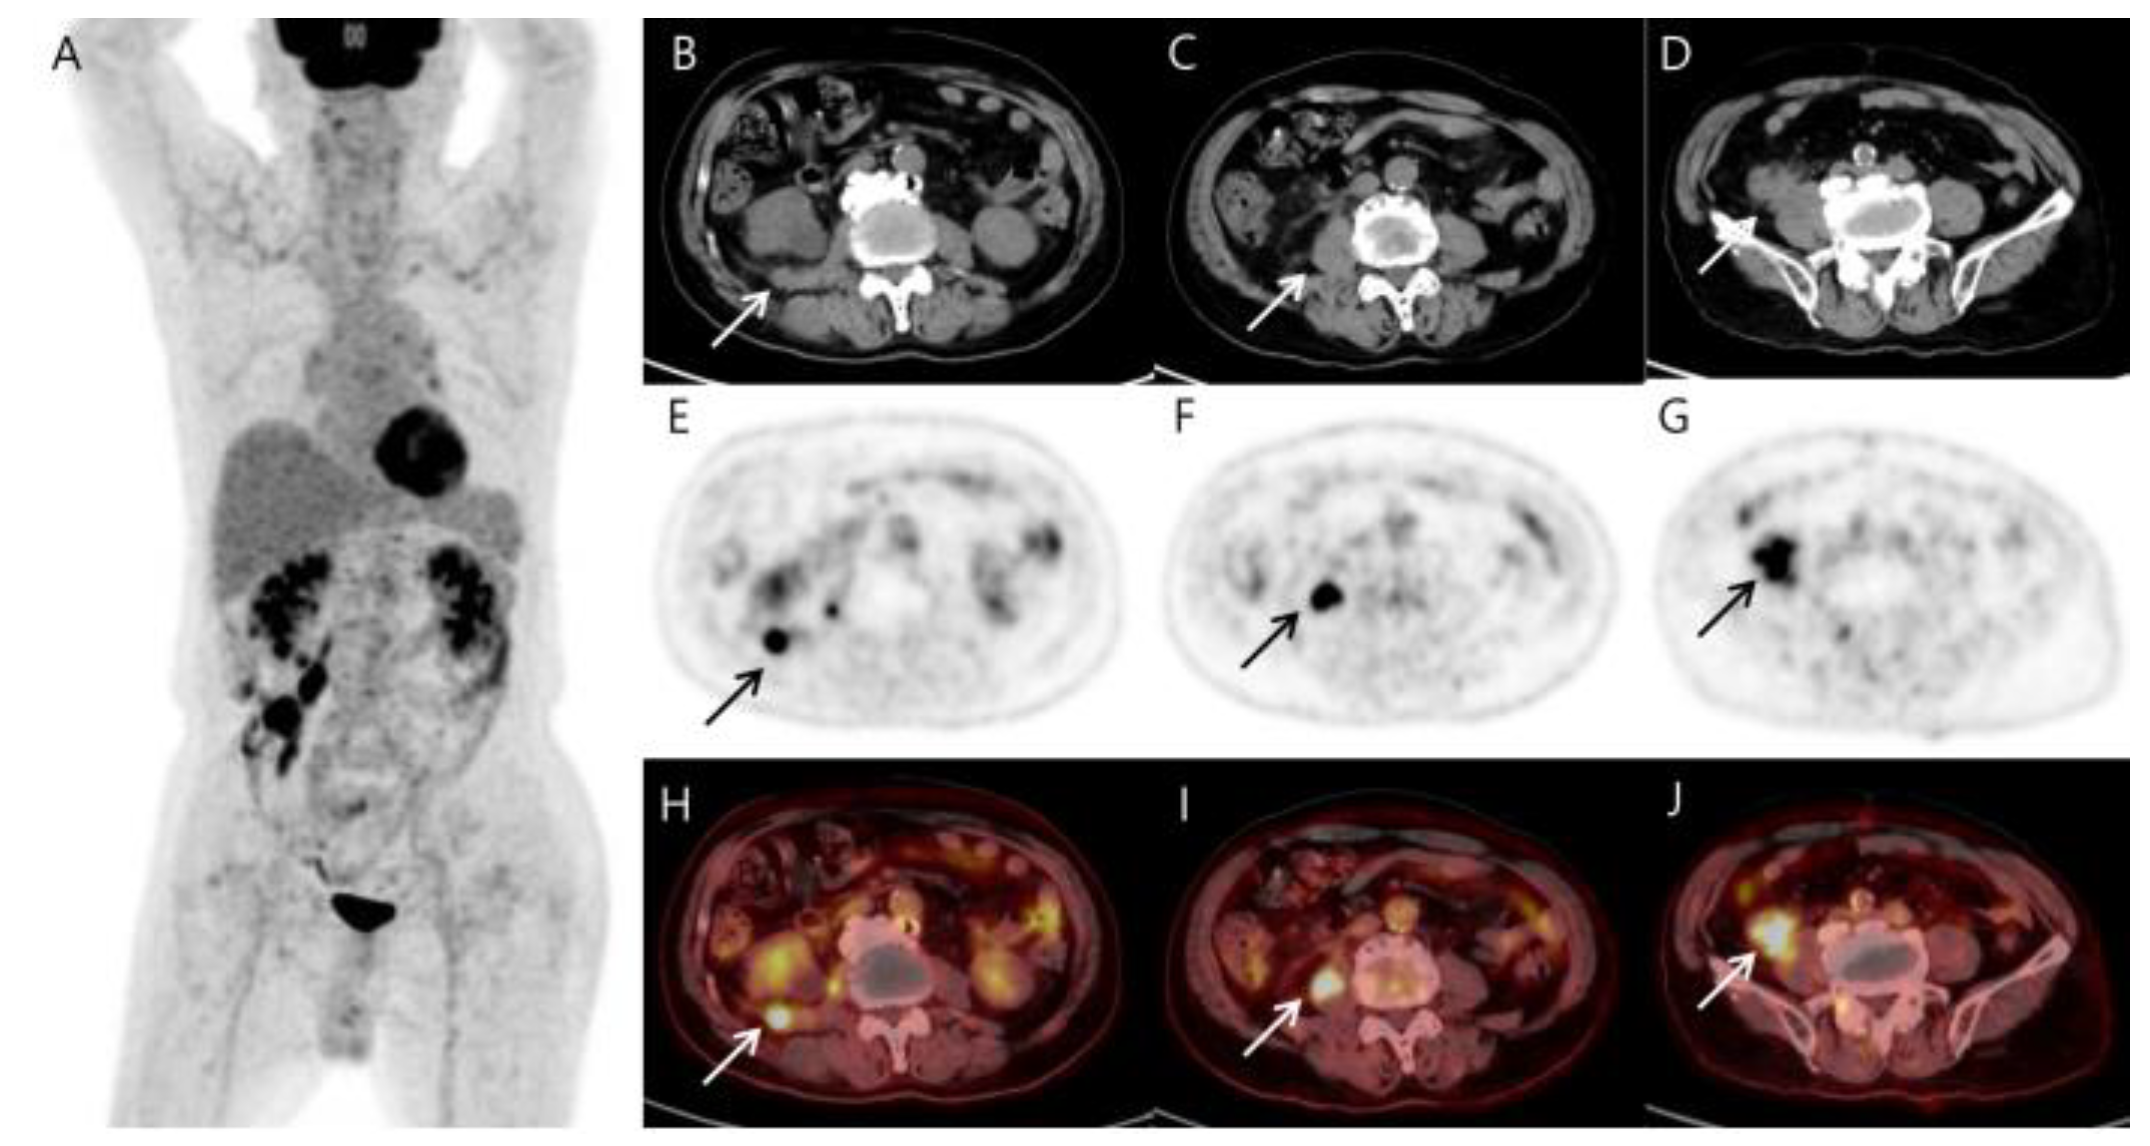

To evaluate the mass, for the staging of the disease, and as a baseline for monitoring the treatment response, 18F-fluorodeoxyglucose (FDG) positron emission tomography/CT (PET/CT) was performed. Due to the purchase cost of the generator that produces 68Ga, 68Ga-PSMA-11 PET/CT is not yet possible at our hospital. Although prostate cancer metastasis was the most suspected differential diagnosis on the abdominal CT, we also had to differentiate between the possibility of sarcoma or recurrent lymphoma, so we performed 18F-FDG PET/CT first. MIP PET (A), axial CT (B–D), corresponding PET (E–G), and fused PET/CT images (H–J) showed a markedly metabolically active soft tissue mass in the distal ileum with invading right psoas muscle. Simultaneously, several hypermetabolic soft tissue nodules in the right retroperitoneal fascia and hypermetabolic mass along the right psoas muscle were also detected. In addition, there was left inguinal hernia (Figure 2). The findings were considered highly suspicious of malignancies such as recurrent lymphoma or soft tissue sarcoma. To confirm the diagnosis, surgical resection of the ileal mass was performed and histopathological and immunohistochemical examinations finally showed histiocytic sarcoma (HS) (Figure 3). The patient has been treated with four cycles of CHOP. The follow-up abdominal CT after three cycles showed a stable disease. A follow-up 18F-FDG PET/CT has not yet been performed and is scheduled to be performed after six cycles.

Figure 2.

MIP (A), CT (B–D), PET (E–G), and fusion PET/CT (H–J) of the 18F-FDG PET/CT images reveal several hypermetabolic soft tissue nodules (arrows) involving the terminal ileum (SUVmax 17.87), right psoas muscle (SUVmax 14.87), and reptroperitoneum (SUVmax 12.22). The terminal ileal mass shows a comet-tail-like pattern of increasing absorption toward the back, suggesting invasion into the psoas muscle. Other than the above-described area, no significant abnormal findings in other parts of the body are included in the image. As shown in the MIP image, it differs too much from the typical prostate cancer metastasis that spreads from bottom to top along lymph nodes to be considered prostate cancer metastasis. Additionally, it is not appropriate to consider it a small intestinal adenocarcinoma and metastasis because the patient has no symptoms. The patient had previously been treated for lymphoma, and based on the 18F-FDG PET/CT findings, we first considered the possibility of recurrent lymphoma or sarcoma.